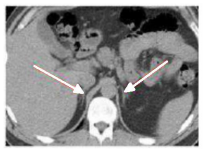

Na radiologia do sistema geniturinário, apresentam-se como duas pequenas massas em forma de Y ou V invertido e se localizam acima dos polos superiores dos dois rins, conforme a imagem abaixo.

Com base no enunciado e na imagem acima, é correto afirmar que se trata de